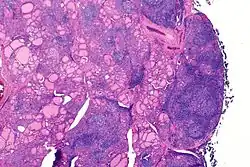

![]() Mikrofotografia tarczycy chorego, w małym powiększeniu. (barwienie H-E) | |

Zapalenie tarczycy Hashimoto, określane także jako przewlekłe limfocytowe zapalenie gruczołu tarczowego, wole limfocytarne[1], choroba Hashimoto[2][1], zapalenie tarczycy autoimmunologiczne, toksykoza Hashimoto (przemijająca), wole limfoidalne, zapalenie tarczycy limfocytarne, wole limfocytowe[1], przewlekłe autoimmunizacyjne zapalenie tarczycy[2] lub przewlekłe limfocytarne zapalenie tarczycy[2][3] (ang. autoimmune thyroid disorder (AITD[4]), Hashimoto’s thyroiditis, chronic lymphocytic thyroiditis; łac. thyroiditis Hashimoto, thyroiditis lymphocytica chronica) – najczęstszy rodzaj zapalenia tarczycy i najczęstsza przyczyna pierwotnej niedoczynności gruczołu tarczowego; jest to choroba o podłożu autoimmunologicznym, często współistnieje z innymi chorobami autoimmunologicznymi[5]. Charakteryzuje się rozlanym naciekiem limfatycznym w obrębie gruczołu tarczowego z centrami rozwoju zarodkowego. Następuje zwłóknienie i atrofia miąższu tarczycy, a w niektórych komórkach pęcherzykowych zmiany eozynofilowe tarczycy[4]. Uważa się ją za najczęstszą chorobę autoimmunologiczną[6], najczęstsze zaburzenie endokrynologiczne[7][6], a także najczęstszą przyczynę niedoczynności tarczycy[8][9][3].

Do charakterystycznych cech choroby należą limfocytowe (limfocyty T, działające destrukcyjnie na miąższ gruczołu tarczowego[5]) nacieki w obrębie tarczycy[12][27][5][2] (obraz w badaniu USG bywa określany jako tarczyca „wygryziona przez mole”, typowo w opisie stwierdza się bardzo niejednorodną, obniżoną, echogeniczność, nacieki podścieliska i wzmożone unaczynienie[40]), obecność (limfocyty B aktywowane przez limfocyty T podlegają przekształcaniu w plazmocyty i produkują przeciwciała[5]) przeciwciał przeciwko tyreoglobulinie (anty-TG; TgAb, anti-thyroglobulin antibody) oraz tyreoperoksydazie (anty-TPO; TPOAb, anti-thyroid peroxidase antibodies) w surowicy[2][12][3]. W obrębie gruczołu tworzą się pęcherzyki limfoidalne z centrami rozrodczymi. Miąższ ulega zwłóknieniu i zanikowi[27]. Apoptotyczne zniszczenie komórek tarczycy powoduje upośledzenie syntezy hormonów[41]. W gruczole obecne są duże komórki pęcherzykowe z obfitą ziarnistą cytoplazmą kwasochłonną (komórki Hürthla, komórki Askanazy'ego, komórki oksyfilne)[27]. Odnotowywane są także okresowe zaburzenia hormonalne[2][12][3]. Gruczoł tarczowy jest blady, o konsystencji od gumowatej do twardej[27]. Chorobie może towarzyszyć zarówno eutyreoza, jak i niedoczynność lub nadczynność gruczołu tarczowego[2]. Nadczynność tarczycy w przebiegu przewlekłego zapalenia tego gruczołu, występuje w przejściowej, krótkotrwałej formie w początkowym okresie choroby i jest wynikiem wydostawania się z uszkodzonych przez proces zapalny pęcherzyków tarczycy nadmiernej ilości utworzonych wcześniej hormonów[2][12][3].